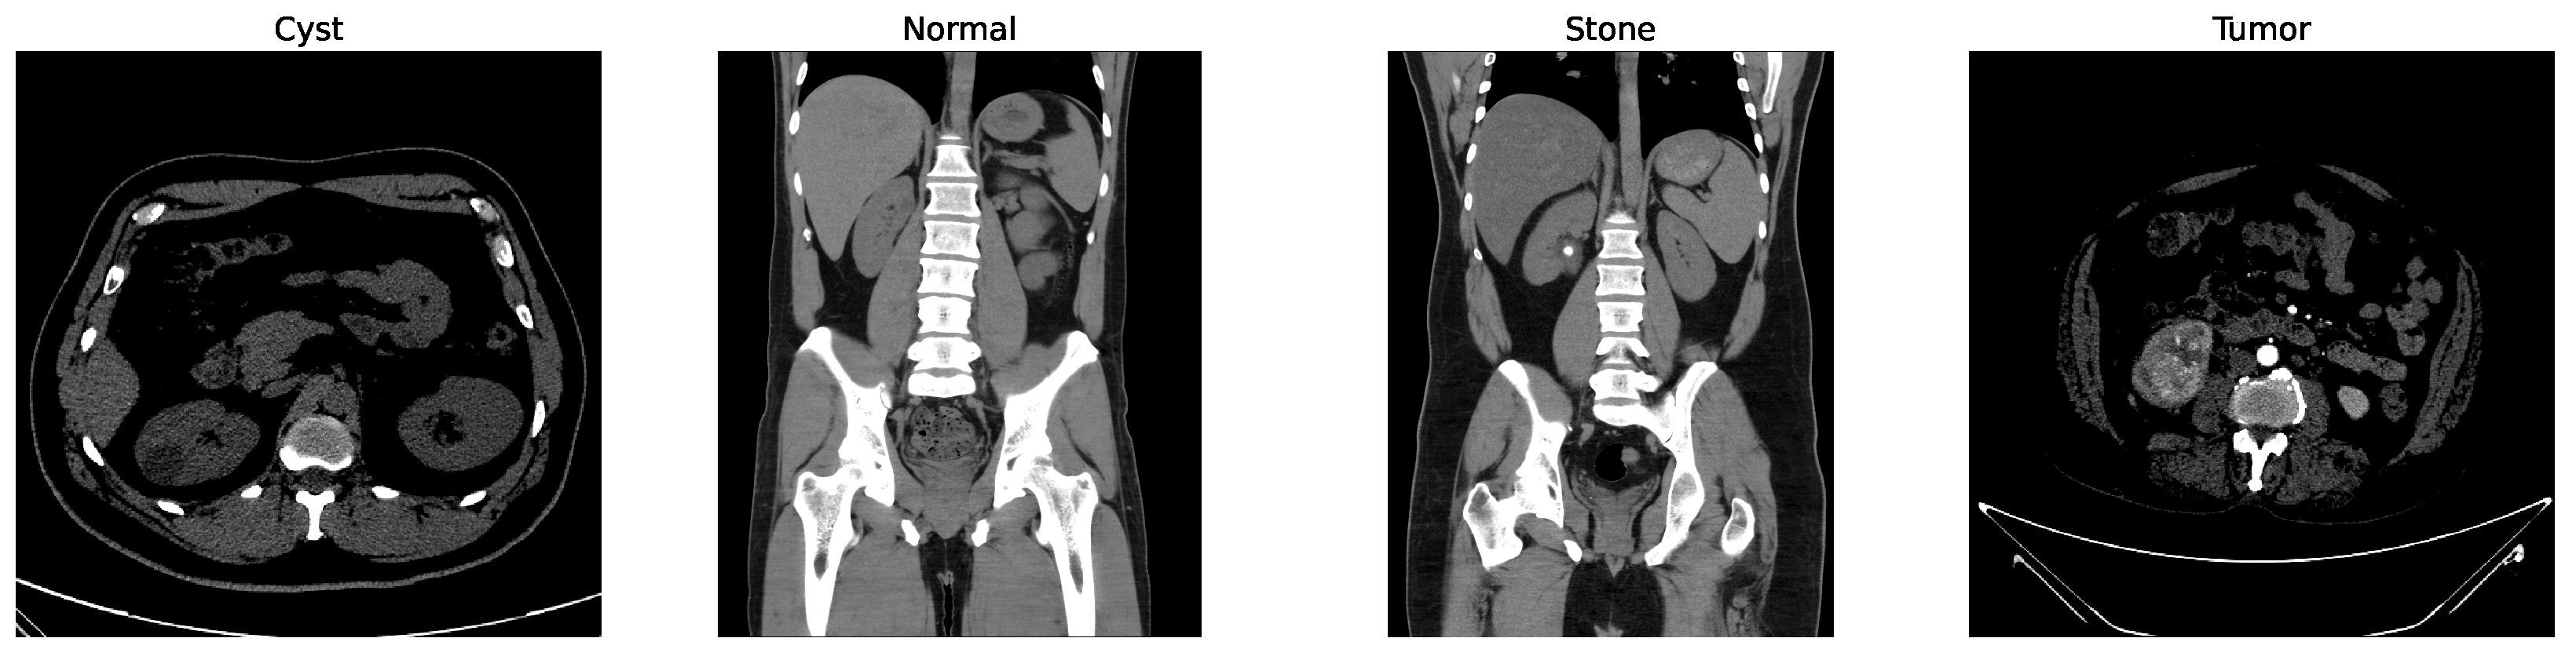

As shown in Figure 8, the confusion matrix of the proposed hybrid model on the baseline dataset is presented below.

Figure 8.

Confusion matrix of baseline dataset.

In the matrix, the diagonal elements represent correctly classified instances, and the rest of the elements indicate misclassifications. The incorrectly classified numbers are 18, 18, and 21 for baseline, Dataset A, and Dataset B, respectively. Although the model performs consistently well across all datasets, a slightly higher misclassification rate is observed in the stone class. This is mainly attributed to the smaller sample size of the stone category, which limits the model’s ability to learn its feature variability, even after applying SMOTE balancing. Additionally, the visual inspection of misclassified cases shown in Figure 9 revealed that some stone images share overlapping visual characteristics with cyst and tumor classes, such as low-contrast textures and irregular boundaries, making them challenging to distinguish even for deep learning models.

Figure 9.

Some incorrectly classified images.